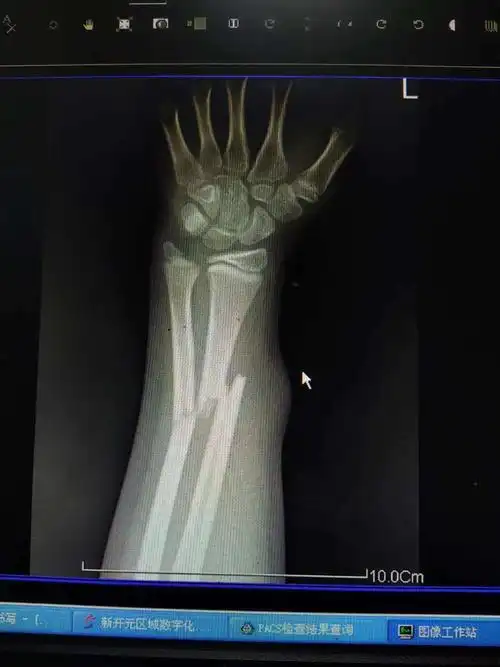

左桡骨小头骨折成这样子严重吗,这是拍的片,以后可以做剧烈运动,可以

儿童尺桡骨远端骨折

左右桡尺骨远端骨折,手法夹板固定 [病例帖]

左尺桡骨双骨折

一例桡骨远端骨折复位 [病例帖]

14岁桡骨近端13处骨折保守治疗一例

尺桡骨远端双骨折,小孩,7岁